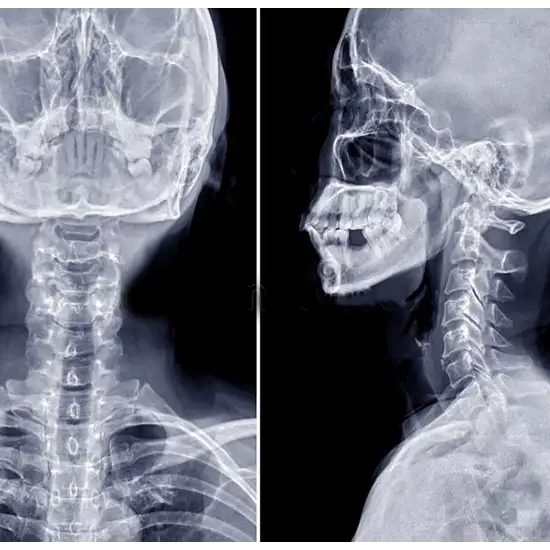

X-ray Cervical Spine AP-LAT Flexion & Extension View

Cervical Spine Flexion and Extension on X-Ray view test helps to visualize the patient’s spinal column's i.e. the first seven cervical vertebrae (C1-C7) (backbone).

Antero-posterior (AP) cervical spine projection is known to be a part of the cervical spine series.

Lateral View: This projection aids in visualizing any pathology that involves the entire cervical spine. i.e.- orthogonal to AP view

AP: This projection aids in visualizing the pathology that is related to the C3-C7 in the anatomical position, thus, demonstrating the following:

Flexion/extension: In this, the x-ray views usually detect the ligamentous lesions that are undetectable by the standard static views.

Lateral View : It is used to discover pathologies in the following conditions: